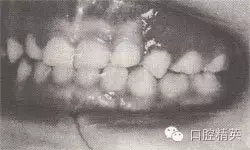

患者,男,4歲,乳牙。磨牙近中關(guān)系。前牙反頜,下頜前突,位置前移。

診斷:乳前牙反頜,安氏Ⅲ類,毛氏Ⅱ¹。

矯治設(shè)計(jì):上頜頜墊式活動矯治器。下頜后退位解剖式頜墊,舌簧推乳上切牙向唇側(cè),調(diào)磨頜墊。

治療時(shí)間:1.5個(gè)月,乳前牙反頜解除,乳切牙達(dá)到正常覆頜、覆蓋。下頜回到正常位置。

圖8-37 安氏Ⅲ類錯(cuò)頜,乳前牙反頜矯治前后面頜像

矯治前咬合圖

矯治后咬合圖